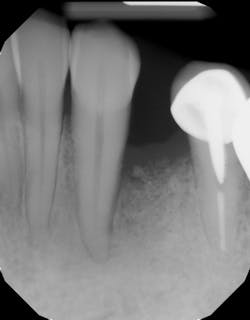

These alveolar bone changes often compromise implant placement due to thin bone volume (figures 2a–2d).

Reduction in quantity and quality of bone can also compromise functional and esthetic outcomes of both implants and fixed bridge restorations (figures 3 and 3a).

This surgical video demonstrates removal of a tooth with loss of buccal plate and grafting of the remaining socket with Geistlich Bio-Oss Collagen and Geistlich Bio-Gide to preserve the ridge for implant placement.